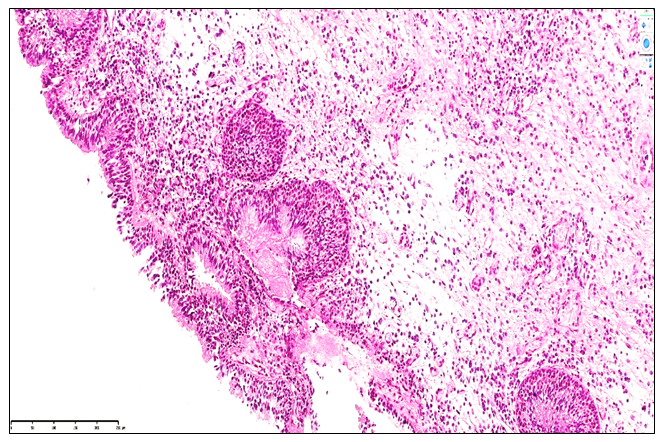

Group 3 (3-5 years post-nasal trauma): During the 3–5 year period following nasal trauma, chronic polypous rhinosinusitis was characterized by pronounced atrophic and structural changes in the nasal mucosa. The mucosal surface exhibited flattening with extensive epithelial metaplasia. Compared to Groups 1 and 2, morphofunctional activity markedly decreased, with basal membrane thickening, vascular congestion, stromal fibrosis, and scattered lymphoid infiltration. Glandular elements were reduced in size, and secretions appeared dense and cystic.Stromal changes included proliferation of fibroblasts, histiocytes, and plasma cells, alongside disorganized collagen bundles. The mucosa showed impaired mucociliary transport due to epithelial flattening, reduced ciliated cells, and accumulation of proteinaceous material. Lymphoid structures of MALT were atrophic, with diminished germinal centers and sparse T- and B-lymphocytes, indicating hyporeactive chronic inflammation.Clinically, these features correspond to the classical presentation of chronic polypous rhinosinusitis with fibrotic and glandular degeneration, cystic polyp formation, vascular sclerosis, and stromal remodeling. In a minority of cases, focal neutrophilic infiltration suggested secondary bacterial involvement. Overall, the findings demonstrate progressive atrophic, fibrotic, and hyporeactive changes in the nasal mucosa during the 3–5 year post-trauma period (see Figure 6). | Figure 6. Chronic polypous rhinosinusitis, Group 3. At 3.5 years post-nasal trauma, the nasal mucosa epithelium exhibits atrophy, desquamation, and focal lymphocytic infiltration. In the glandular stroma, interstitial swellings are observed among lymphocytes. Staining: H&E; Magnification: 10×10 |

In our study, during the 3–5-year period following nasal septum injury, chronic polypous rhinosinusitis was characterized predominantly by atrophic and sclerotic changes. The mucosal epithelium exhibited atrophy, desquamation, and erosive areas. Secretory glands demonstrated cystic dilation and perivascular fibrosis, while stromal eosinophilic and lymphoplasmacytic infiltrates were reduced, accompanied by increased fibroblast and histiocyte proliferation and stromal fibrosis. Small-caliber blood vessels showed signs of neoangiogenesis, and MALT structures were reduced in size. These alterations indicate a hyporeactive inflammatory process and a marked decline in mucosal morphofunctional integrity.